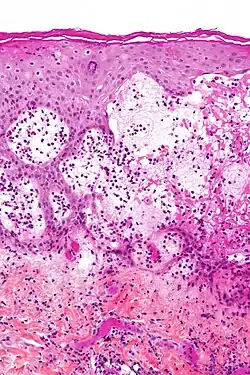

Micrograph of gestational pemphigoid showing the characteristic subepidermal blisters and abundant eosinophils. HPS stain.